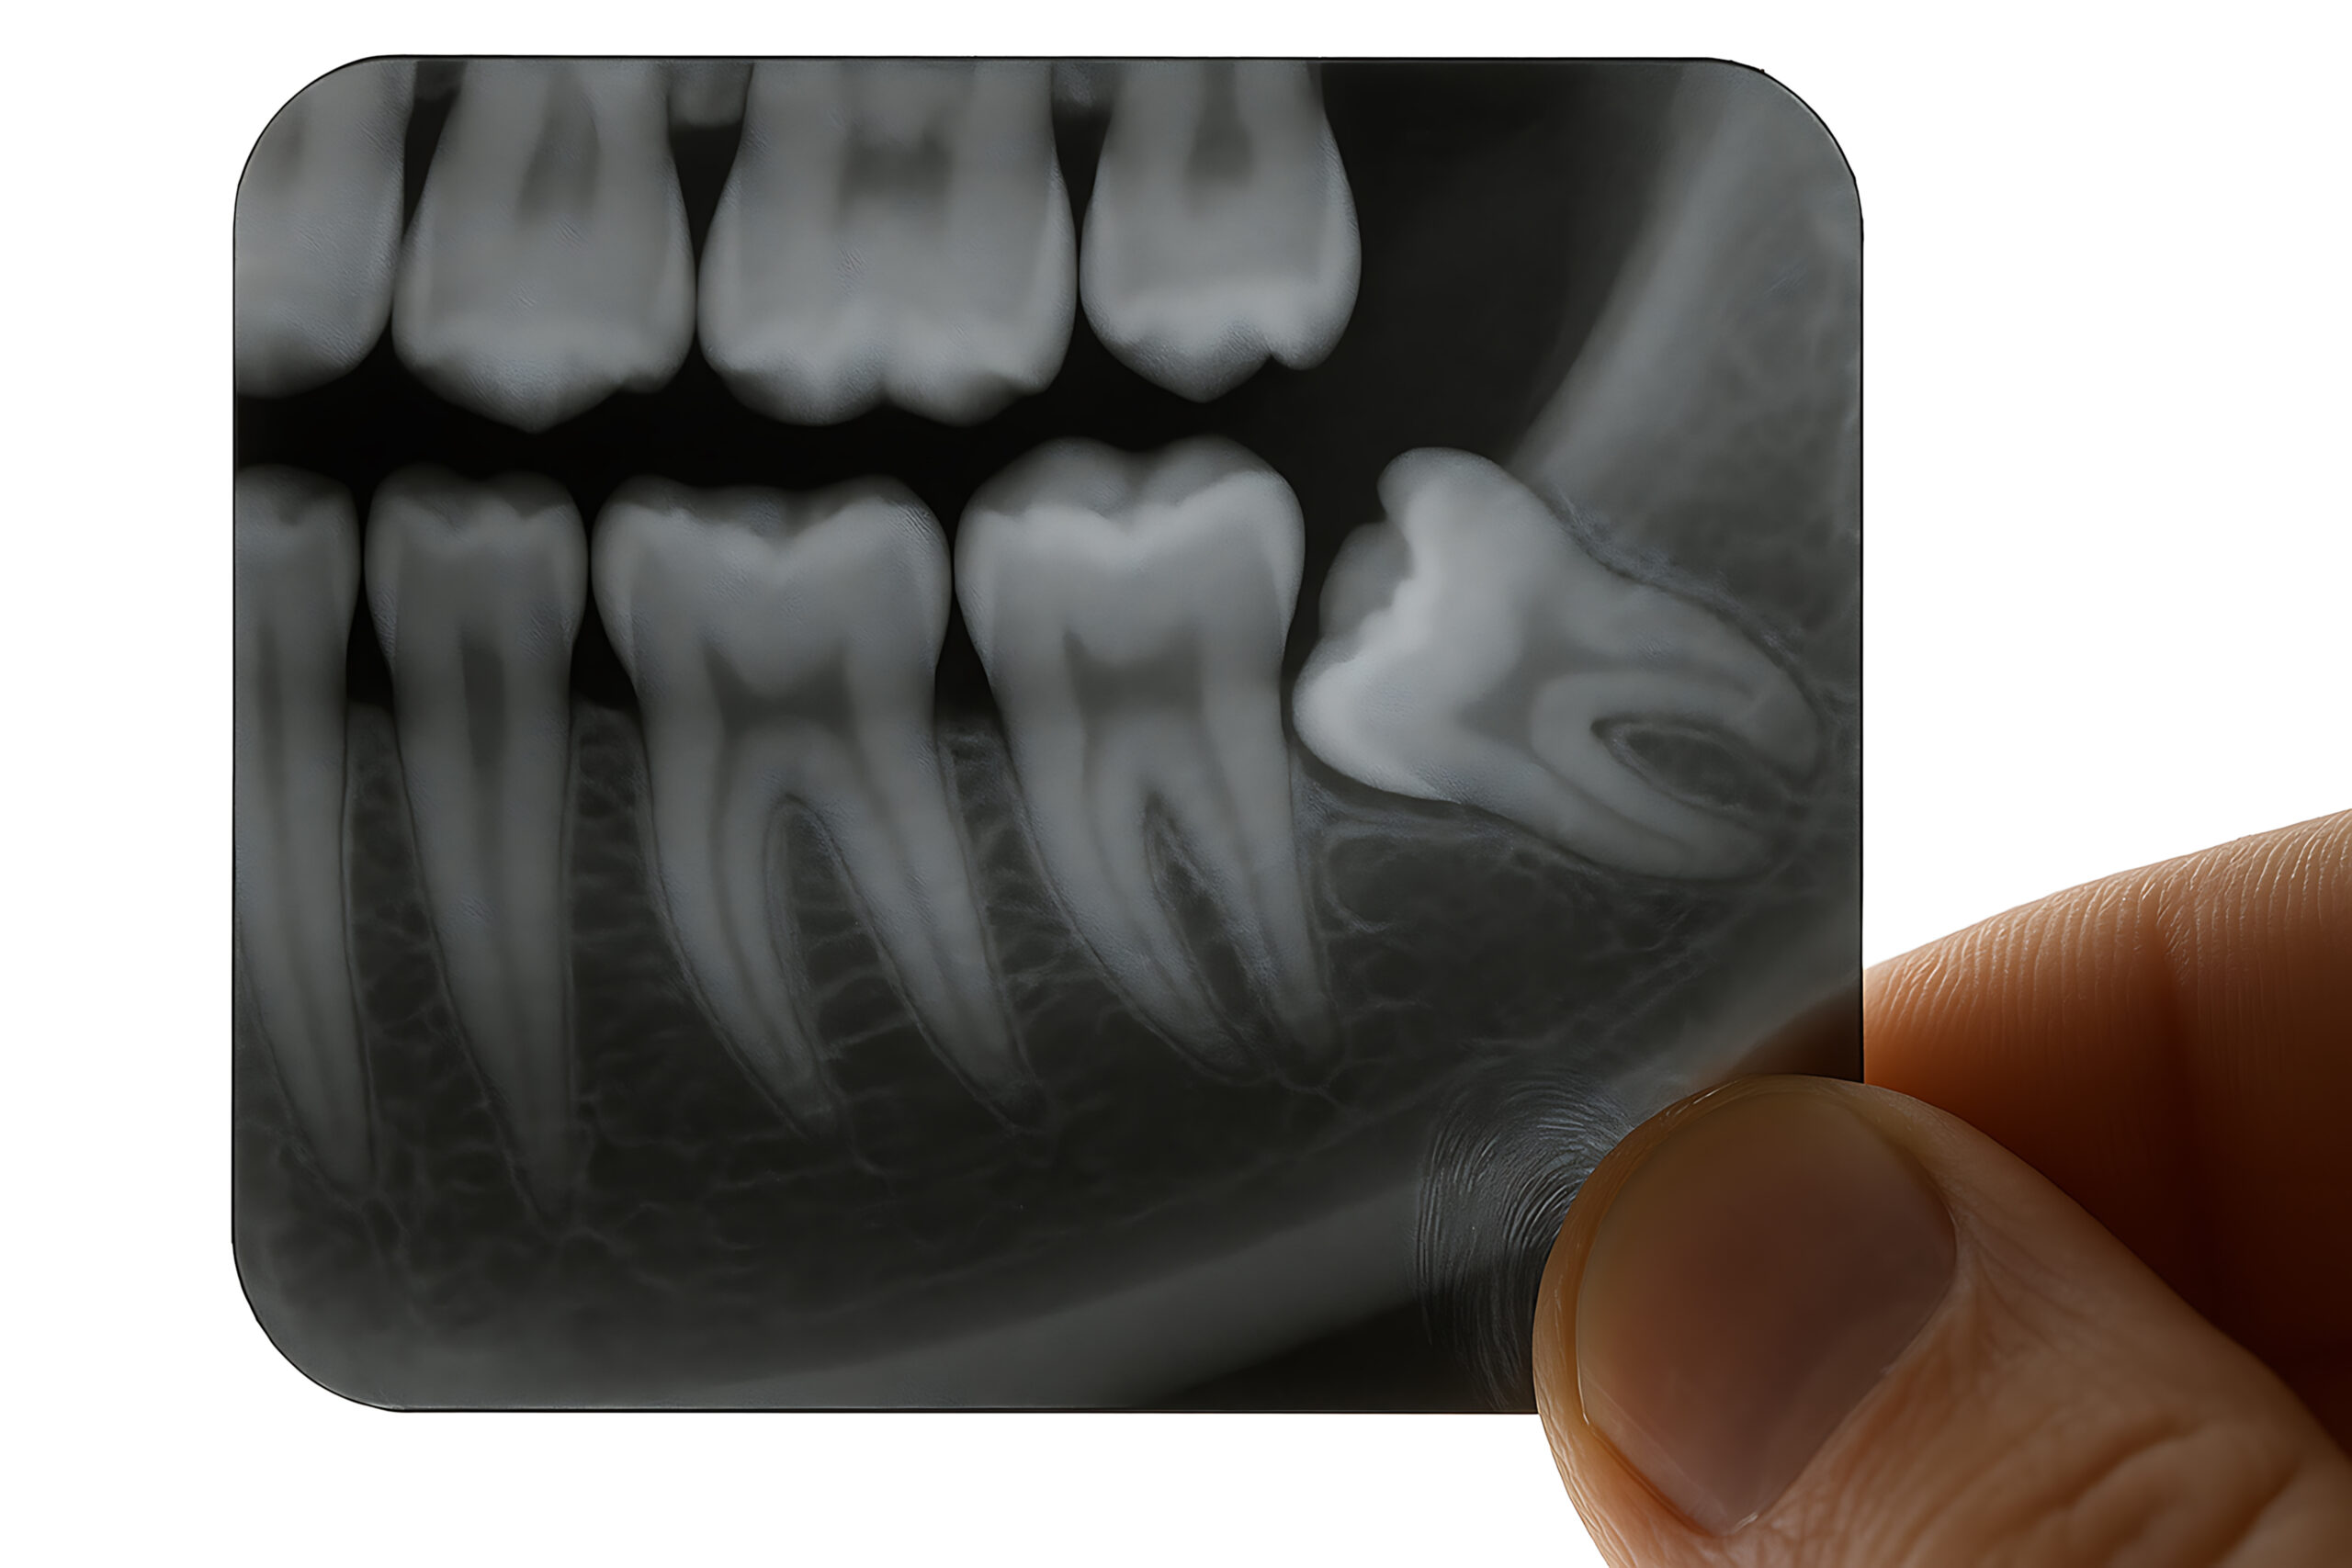

Impacted wisdom teeth can develop cysts or tumors around them, which can damage your jawbone and adjacent teeth. Regular monitoring through X-rays helps identify developing cysts early, and removal of the wisdom tooth eliminates the risk of continued cyst growth.

Dr. Long performs a detailed examination including 3D imaging to assess the position of your wisdom teeth, their relationship to adjacent teeth and nerves, and whether removal is recommended. This thorough evaluation determines the complexity of extraction and helps plan the safest approach for your specific situation.